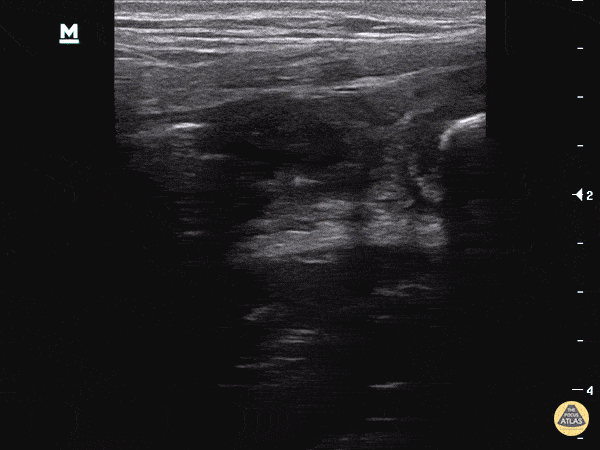

Appendicolith/Fecalith Appendicolith within the lumen, appearing as a hyperechoic structure with shadowing